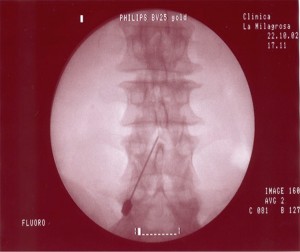

TÉCNICA

El paciente se coloca en  decúbito prono con una almohada en la zona abdominal para disminuir la lordosis lumbar si fuera necesario, se recomienda una visión radiológica antes de decidir si es conveniente o no su empleo. La técnica se realiza con sedación consciente. Se localizan los niveles patológicos con una proyección en AP. Una vez identificados los niveles se elimina el doble contorno de los cuerpos vertebrales con una inclinación del Rx en el plano axial (cráneo-caudal). El arco se va rotando en dirección oblicua ipsilateral a la lesión hasta que aparece en la pantalla la imagen del “scotty dog” . Con esta imagen se introduce la aguja en visión túnel hasta hacer contacto óseo con la unión entre la apofisis articular superior y la apofisis transversa, por encima del ojo del perrito. El punto diana es la parte posterior de la apófisis transversa debajo de la parte medial de su borde superior o la parte media entre el borde superior de la apófisis transversa y el ligamento mamilar. Por último se comprueba la localización de la punta de la aguja con una imagen en  lateral, la aguja debe estar colocada en la línea facetaria, posterior al agujero foraminal y por debajo del disco intervertebral. En algunas ocasiones se puede comprobar la localización de la aguja con una proyección AP, en este caso la punta de la aguja estará localizada en la unión del proceso articular superior y la parte más medial de la apófisis transversa.

Cuando se realiza el tratamiento sobre el ramo medial de L5 hay que tener en cuenta algunas diferencias. El ramo medial a este nivel transcurre en un valle formado por la apófisis articular superior del sacro y el ala del mismo. Para conseguir ver este punto es necesario realizar una rotación en el plano axial del Rx para distanciar la creta ilíaca. Cuando se consigue esta imagen la aguja se dirige en visión túnel a la parte más alta del valle, que está formada por el ala del sacro y su apófisis articular superior.